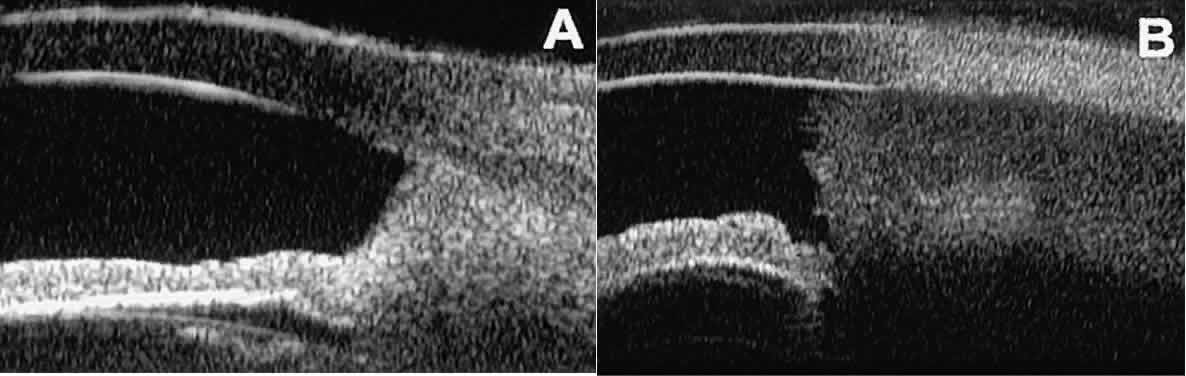

Postoperative UBM imaging of the anatomic changes caused by glaucoma surgery often helps to explain mechanisms of success and failure of the various surgical procedures (Fig. 12).3,4 After laser iridotomy, UBM can show whether the iridotomy is partial thickness (see Fig. 12A) or full thickness (see Fig. 12B) and whether the plane of curvature of the peripheral iris has changed compared with the pretreatment findings. After trabeculectomy (see Fig. 12C), UBM can show whether the scleral aperture is patent or blocked internally, whether the peripheral iridectomy is open or blocked, and whether the filtering bleb is flat, shallow, or deep.9 After tube shunt surgery (see Fig. 12D), UBM can show the position of the tip of the tube and whether its orifice is open or plugged.

Fig. 12. UBM features in glaucomatous eyes after treatment or filtering surgery. A. Incomplete peripheral iridectomy created by laser. B. Full-thickness peripheral iridectomy created by laser. C. Postoperative features of trabeculectomy including peripheral iridectomy, inner scleral defect, thin residual scleral flap, and overlying conjunctival filtering bleb. D. Tube shunt projecting radially into anterior chamber; note that the tube “shadows” deeper structures.

After any type of glaucoma filtering surgery,10 UBM can be used to detect and evaluate the extent of postoperative complications such as ciliochoroidal effusion and cyclodialysis.3,4 In ciliochoroidal effusion (Fig. 13A), UBM shows the ciliary body to be edematous and separated from the sclera by a sonolucent collection of supraciliary fluid. Many ciliochoroidal effusions that are too limited in extent to be detectable by indirect ophthalmoscopy and slit lamp biomicroscopy can be imaged by UBM. In cyclodialysis (see Fig. 13B), UBM shows a well-defined separation between the uveal tissue and the sclera in the region of the scleral spur. The width of the cleft is usually assessed best by means of limbus-concentric images through the region of interest.

Fig. 13. Complications of intraocular surgery. A. Postoperative ciliochoroidal effusion appears as slitlike spaces filled with serous fluid posterior to scleral spur. B. Postoperative cyclodialysis appears as complete separation of iris and ciliary body from sclera in region of scleral spur.